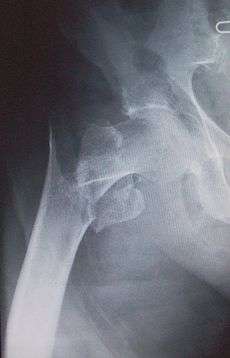

Intertrochanteric hip fracture in a 17-year-old male

Medial fracture in a 92-year-old woman

X-rays of the affected hip usually make the diagnosis obvious; AP (anteroposterior) and lateral views should be obtained.